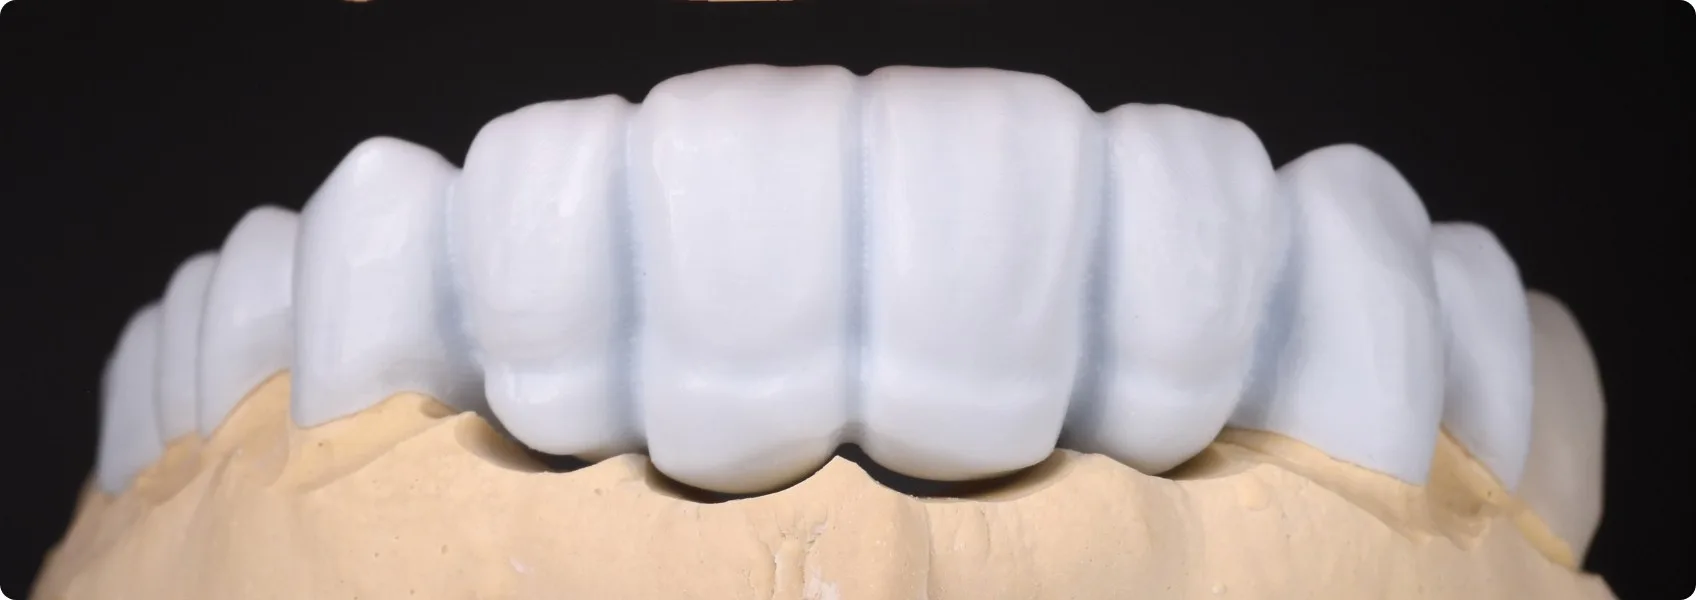

Dopiero wtedy możemy przejść do dalszych kroków. Technik dentystyczny drukuje model nowego zgryzu Pacjenta (tzw. wax-up), który będzie naszym wzorcem do dalszej pracy.

W NDC Pacjent aktywnie uczestniczy w projektowaniu swojego nowego uśmiechu. Zanim przystąpimy do jakichkolwiek nieodwracalnych działań na zębach, tworzymy wstępną wizualizację przyszłej odbudowy. Można ją założyć i przejrzeć się w lustrze!

Jest to tzw. mock-up, czyli tymczasowy model nowych zębów, który umieszczamy w ustach Pacjenta na jego własnych zębach, bez żadnej ingerencji w nie. Mock-up możemy po chwili ściągnąć.

To jak „przymiarka uśmiechu”. Pacjent na tym etapie może ocenić kształt, wielkość, a nawet funkcję przyszłej rekonstrukcji i zgłosić wszelkie uwagi. To bezcenny etap, który eliminuje ryzyko rozczarowań.